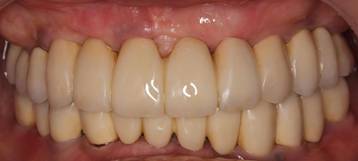

術前。62歳男性。仮の歯の入っている上顎前歯部は抜歯するしかない状態。右下がない為右上臼歯が伸びだしていました。入れ歯では咬めないのでインプラントを希望され紹介されて来院されました。

63歳術後。よく噛めるようになり喜んでいただけました。

術前のパノラマレントゲン写真。仮歯を支えている4本の歯は根が残っているだけで抜歯の必要がありました。

63歳術後のパノラマレントゲン。インプラントはスプラインツイスト